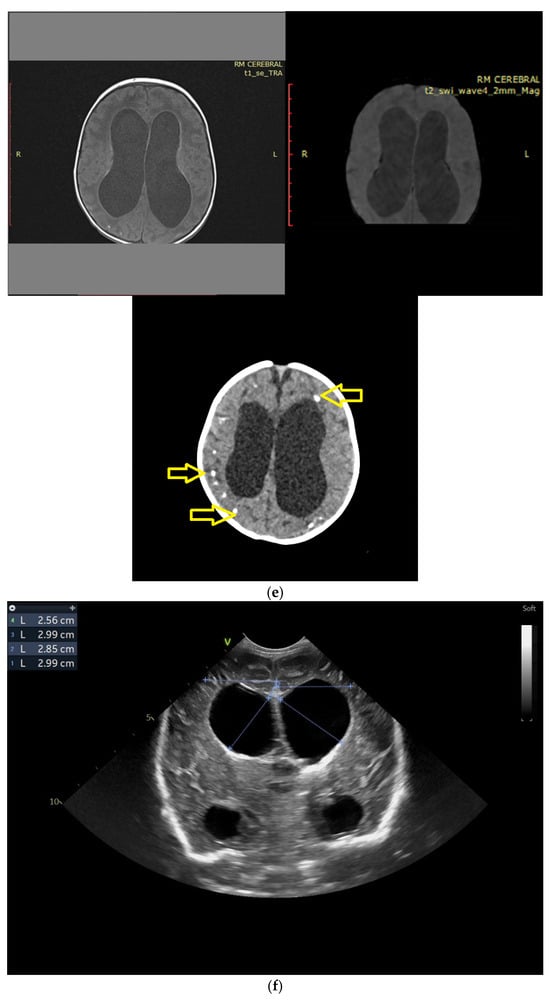

(a) Cranial ultrasound. Coronal view. Lateral ventricles and third ventricle enlargement. L1, L2—Levine index measurement. L3, L4—posterior horn of the lateral ventricles’ width measurement. L5—third ventricle width measurement (personal image collection). (b) Cranial ultrasound. Sagittal view. Enlarged third and fourth ventricles. L1, L2—third ventricle measurements. L3, L4—fourth ventricle measurements (personal image collection). (c) Cranial ultrasound. Sagittal view. Enlarged lateral ventricles. Up—left ventricle. Down—right ventricle (personal image collection). (d) Cranial ultrasound. Coronal view. Punctuate hyperechoic images were observed in the right lobe (personal image collection). (e). Up left—MRI T1 sequence. Up right—MRI T2 sequence—susceptibility weight imaging (SWI). Down—CT scan. Transversal view. Yellow arrows—multiple calcifications can be seen in the CT scan (personal image collection). (f) Cranial ultrasound. Coronal view. Lateral ventricles. L1, L2—Levine index measurement. L3, L4—anterior horn width measurement. Blue arrow—intraventricular shunt (personal image collection). (g) Cranial ultrasound. Sagittal view. Thalamo-occipital distance measurements. Up—right ventricle. Down—left ventricle (personal image collection).

At six weeks after birth, an MRI scan was performed, while a CT scan was performed at 14 weeks of life, both providing valuable information regarding the sequelae of Toxoplasmosis (Figure 4e). Even though a few signs were observed on the MRI, the CT scan better outlined the presence of the parenchymal calcifications. A neurosurgical intervention was intended, a ventricle puncture was performed, and a shunt was placed in the right ventricle. The cranial ultrasound at two months of life did not show notable improvements, however (Figure 4f,g). The neurological examinations showed axial hypotonia and limb hypertonia.